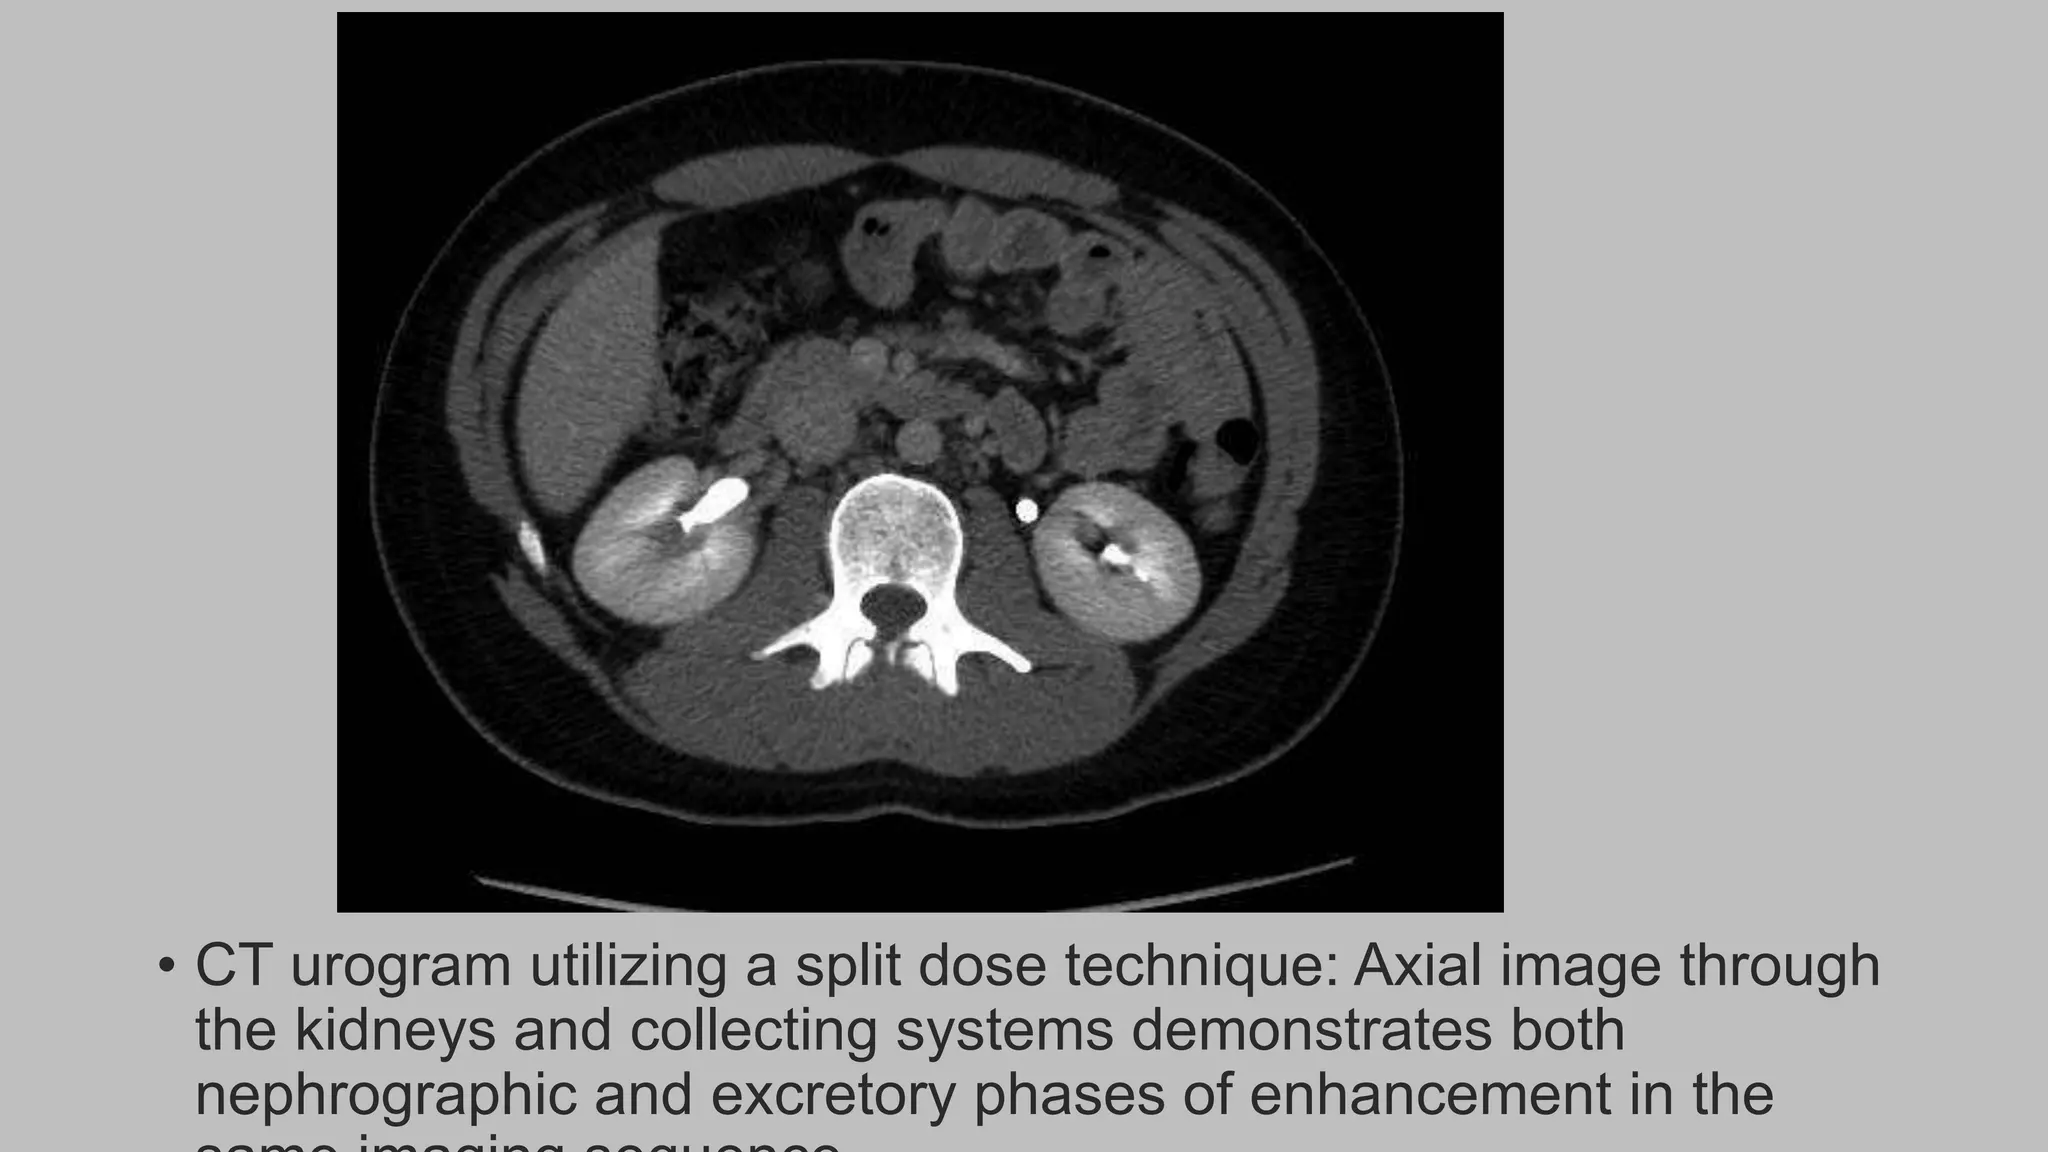

• CT urogram utilizing a split dose technique: Axial image through

the kidneys and collecting systems demonstrates both

nephrographic and excretory phases of enhancement in the

• CT urogram utilizing a split dose technique: Axial images

displayed with wider window settings are suitable for display of

the opacified collecting systems and urinary tract calculi.

• CT urogramutilizing a split dose technique: Axial image through the kidneys and collecting systems demonstrates both nephrographic and excretory phases of enhancement in the

• CT urogramutilizing a split dose technique: Axial images displayed with wider window settings are suitable for display of the opacified collecting systems and urinary tract calculi.